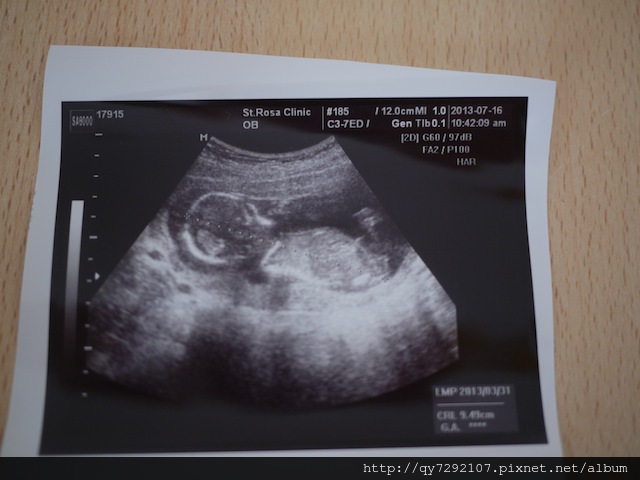

前兩天我經歷了差點失去Pony的驚魂與恐懼!上禮拜帶妹醬去未來的幼稚園參觀體驗,回家之後深感身體不適,預估自己可能是中暑了,隔天一早馬上高燒到40度,看了醫生吃了退燒藥,昏睡了一整天,隔天一樣感覺身體很虛弱,婆婆趕來幫我照顧妹醬,第二天是星期日,T先生卻要加班,我不好意思再麻煩婆婆來幫忙,獨自照顧妹醬,到了晚上就一直感覺身體很不適,半夜起來上廁所時,發現我出血了!!我全身發抖,心想:怎麼會這樣?!怎麼會出血?都已經要4個月了,應該要很穩定才是,回到床上,我搖醒T先生害怕的眼淚直流,一整個晚上宮縮不停,有好幾次我都覺得我快撐不下去了,Pony快被我不停歇地宮縮給擠出來了,我不停地禱告,祈求上帝體諒一個母親渴望孩子的心情,幫助我渡過每一次的宮縮,我不停的對Pony喊話,告訴他/她我有多麼期盼他/她的到來,希望他/她可以努力留在我體內,我隔天一早,我們直奔醫院,當醫生把超音波探頭放在我的肚皮上,我清楚的看見Pony小小的人形還有一閃一閃的心跳,我頓時安心了不少,眼眶也濕了,醫生說:baby很好很健康,我們來聽聽胎心音。聽到Pony砰!砰!砰!的胎心音時,我感動的哭了…從去年到現在,懷孕第四次,感謝妹醬平安出生之外,經歷了2次小產,我都只有經歷到前期辛苦的害喜孕吐與最後的失去失望,都沒有最後孩子抱在懷中的喜悅,這一次,終於~讓我聽到baby的心跳了!這個美妙的音樂,是給我一直不放棄擁有第二個孩子最好的鼓舞!

因為羊膜瓣的問題,讓我徹夜難眠,我上網找了風評很好的”幸福婦產科”診所,會診了王醫師,王醫師說:baby已經18週大,骨骼發育良好,加上妳的羊膜瓣在邊邊,baby去勾到的機率真的不高,要我放寬心,好好享受現在剩下的孕期。雖然王醫師不能掛保證,現階段台灣對於羊膜瓣也無法做什麼處置,建議我若擔心,可以在22週時做高層次超音波,我只能保有信心,相信Pony,對她信心喊話了!因為如此,我跟T先生也決定讓Pony在台灣出生。

自從決定在台灣生產之後,身體狀況越來越好,也開始吃比較多,身心狀況似乎越來越順利,難道真的是像人家說的,孩子會自己決定出生的時間與地點?!在台灣我依然嚮往“溫柔生產”,今天跟姐姐拜訪了主張溫柔生產的樂寶兒,也參觀了水中生產的房間,如果我身體狀況允許,Pony也配合,還是希望以水中生產的方式迎接Pony的到來,會診了許逸欣醫師,我跟姐姐都非常喜歡她,這就是所謂的醫生緣吧?!今天謝謝許醫師的耐心看診,她幫我看超音波看得非常仔細,Pony的10根手指和腳趾都算的清清楚楚,頭部,心臟和內臟也一併看了,Pony非常健康活潑,我憂心羊膜瓣的問題,也終於放下了!許醫師也說:不用花錢做高層次超音波了。關於Pony的性別,Pony有一瞬間打開腳給我們看一下,之後就害羞的合起來了,許醫師說:看起來比較偏向女生,沒有看到小雞雞喔!不管是男孩女孩,今天我最開心的就是Pony四肢健全,身體健康。Dear Pony:要跟媽媽一起繼續加油喔!